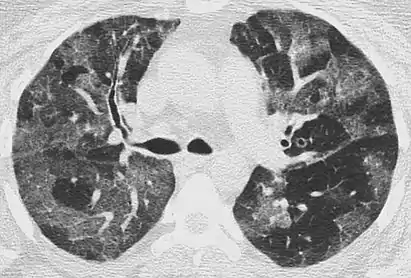

CT image showing diffuse GGOs throughout both lungs. An abscess is also noted in the right lung (screen left). - Adenocarcinoma in situ of the lung

The diffuse pattern typically refers to GGOs in multiple lobes of one or both lungs. Broadly, a diffuse pattern of GGO can be caused by displacement of air with fluid, inflammatory debris, or fibrosis. Cardiogenic pulmonary edema and ARDS are common causes of a fluid-filled lung. Diffuse alveolar hemorrhage is a rarer cause of diffuse GGO seen in some types of vasculitis, autoimmune conditions, and bleeding disorders.[6]

Inflammation and fibrosis can also cause diffuse GGOs. Pneumocystis pneumonia, an infection typically seen in immunocompromised (e.g. patients with AIDS) or immunosuppressed individuals, is a classic cause of diffuse GGOs. Many viral pneumonias and idiopathic interstitial pneumonias can also lead to a diffuse GGO pattern. Radiation pneumonitis, a side effect of pulmonary radiation therapy, can lead to pulmonary fibrosis and diffuse GGOs.[6]